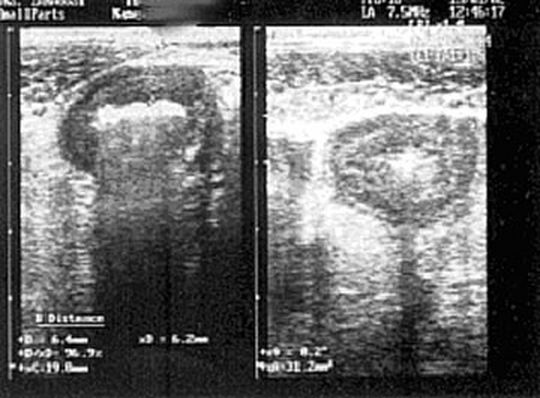

5.7. Lesiones inflamatorias o isquémicas